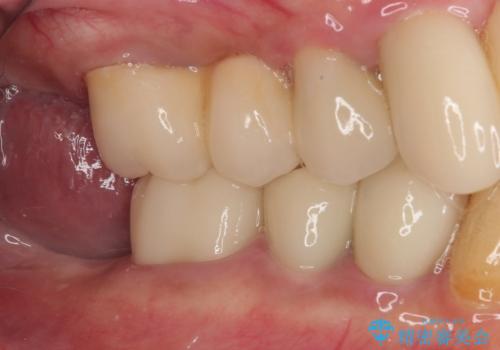

- 奥歯に装着していたクラウンが外れてしまったとのことで来院された患者様です。

診察したところ、歯根に破折線が確認され抜歯が必要な状態でした。

歯肉や歯槽骨の状態は良好であったため、抜歯即時埋入インプラントによる補綴治療を行うこととしました。

抜歯、インプラント埋入、仮歯の装着を1度に行うことができ、治療終了までわずか3か月で終えることができました。